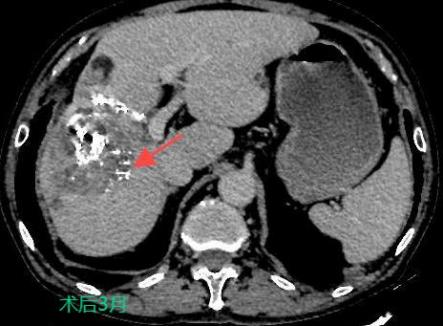

三、肝癌的介入治療

TACE/HAIC:經肝動脈灌注化療栓塞(TACE)、肝動脈內灌注化療藥物(HAIC)是在不開刀暴露腫瘤病灶的情況下,在皮膚上做直徑幾毫米的切口,在影像設備的引導下,導絲和導管插入肝臟腫瘤供血管,注入栓塞劑和化療藥物,使肝臟腫瘤內化療藥物濃度提高,并減少全身的藥物總濃度,達到提高化療效果并減少毒副作用的目的。對于無法手術切除的巨塊型肝癌、肝內多發肝癌病灶、肝癌結節破裂出血有良好的治療效果。

肝癌的介入治療